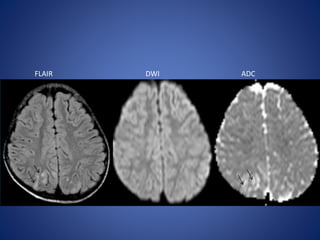

FLAIR DWI

7 Months male…………………………………………….

FLAIR DWI 7 Monthsmale…………………………………………….